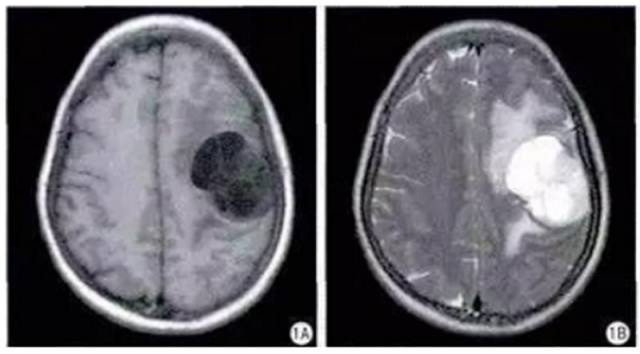

病例一:男性,83岁,头痛

病理:混合型脑膜瘤

T1、T2显示鞍区实质性等信号肿块,垂体柄受压紧贴视交叉膈面。增强呈明显均匀强化,动态增强信号强度表现为早期快速升高,中后期缓慢下降。